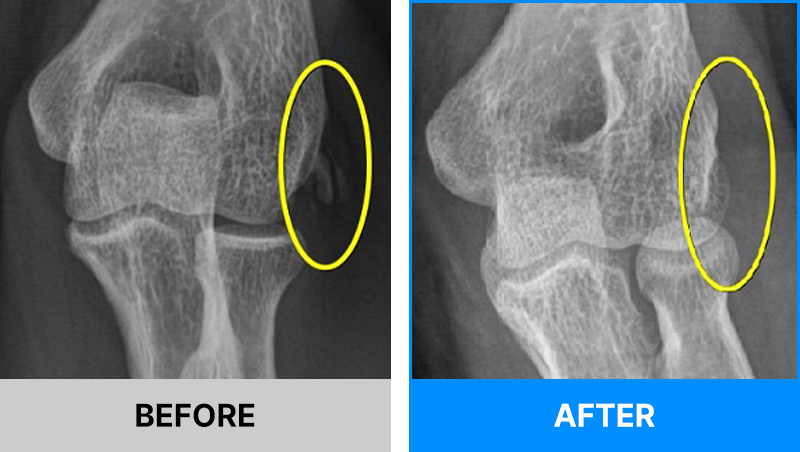

왜 당일 입퇴원 수술일까요?

오래 입원할 필요가 없기 때문입니다.

서울거탑정형외과에서는 전신마취, 척추마취가 아닌

국소부분마취(신경차단) 및 수면 마취를 통해 수술을 시행합니다.